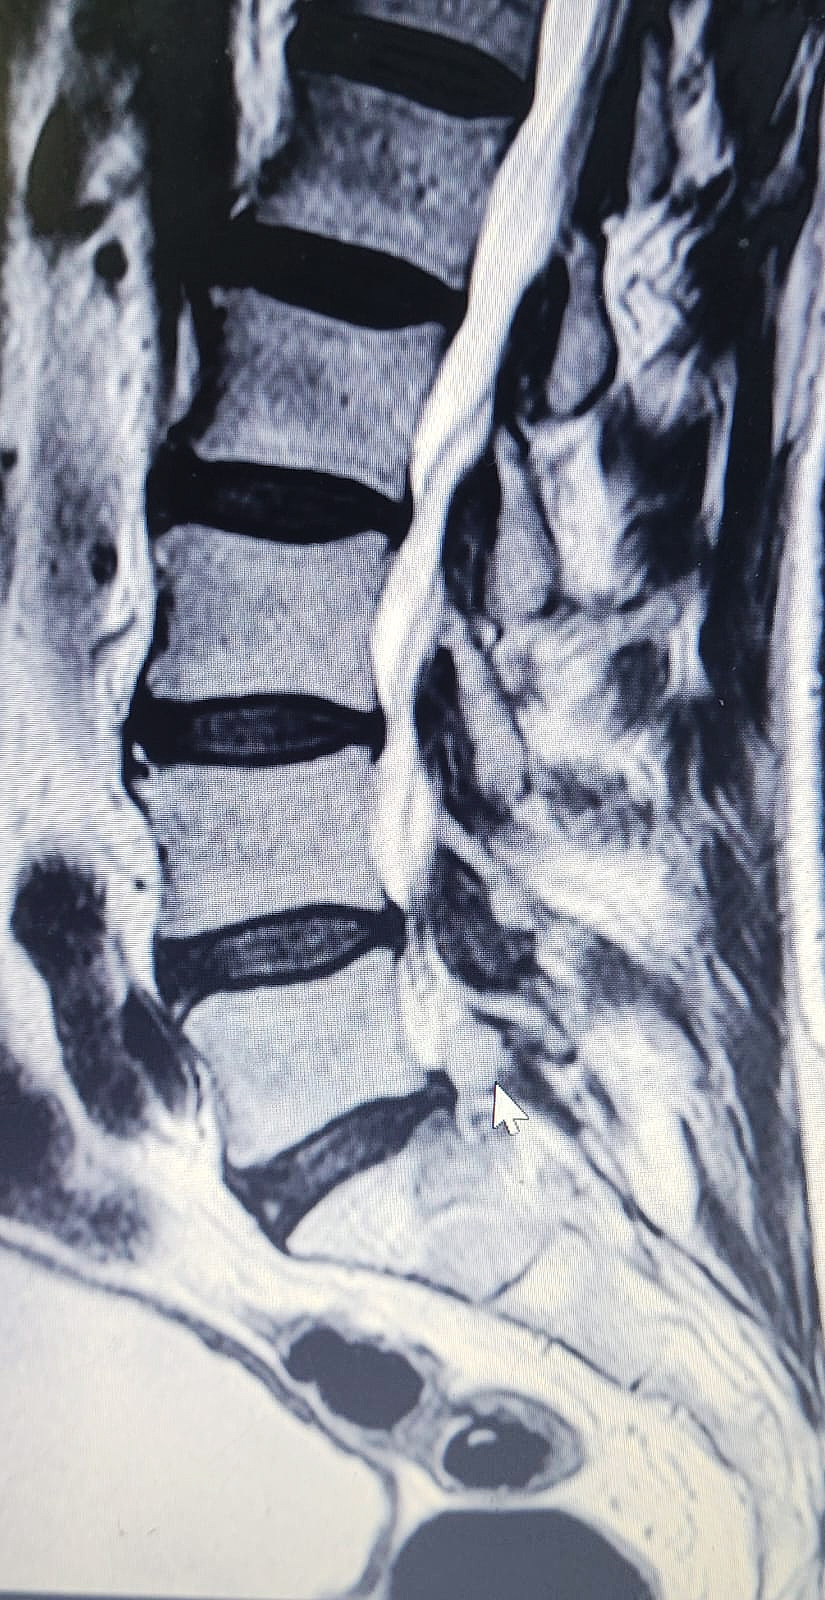

Una resonancia magnética de columna lumbar evidenció la presencia de un quiste facetario sinovial a nivel L5-S1 derecho, el cual comprimía la raíz nerviosa L5, generando los síntomas incapacitantes.

Ante este diagnóstico, se procedió a una cirugía de exéresis del quiste y liberación radicular mediante un abordaje tubular mínimamente invasivo. El procedimiento fue liderado por el neurocirujano Dr. Néstor Romero, quien explicó que la intervención fue un éxito: